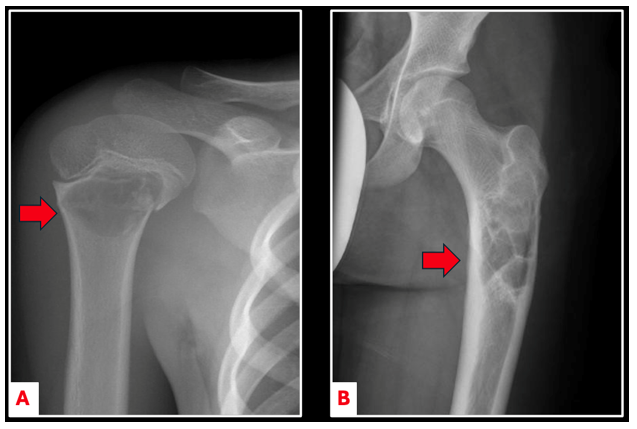

On imaging, unicameral bone cysts (UBCs) are typically seen in the center of the bone, with thinning of the surrounding bone wall (cortex) (Figure 1). UBCs can grow large and cause the bone to expand, making it thin and weak. Sometimes, small pieces of bone can break off and fall into the cyst cavity — a feature known as the “fallen leaf sign” (Figure 2A).

Figure 1. Anterior-posterior imaging of a minimally displaced pathologic fracture through a UBC found in the proximal humerus (A). UBCs can also arise in major weight bearing bones such as the proximal femur (B).